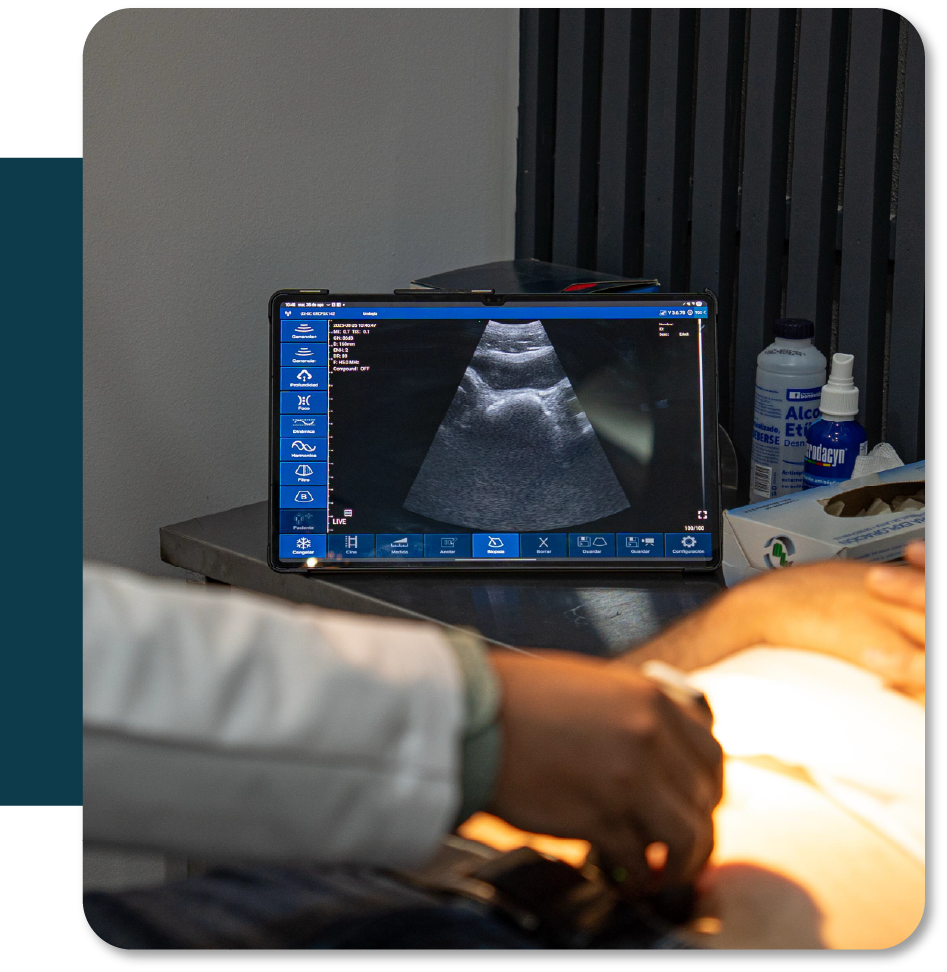

Ureteroscopia Láser

Procedimiento mínimamente invasivo que utiliza un endoscopio y láser para localizar y fragmentar cálculos en el uréter o el riñón.